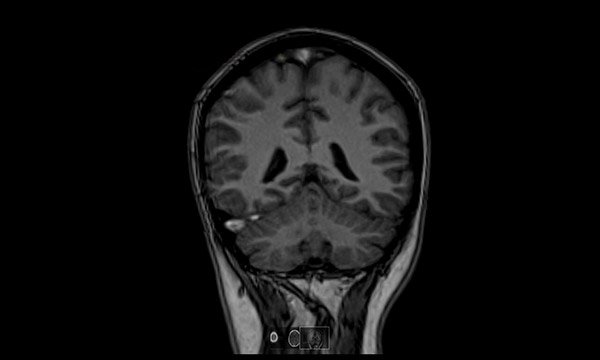

Causes and variability of presenting symptoms, diagnosis and treatment options for CVT